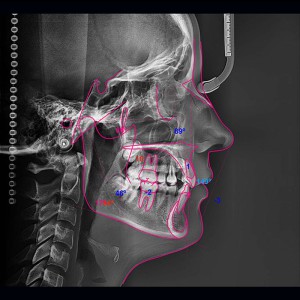

SERVICIOS 2D